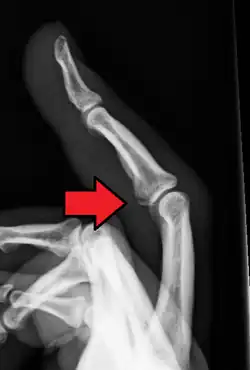

Avulsion fracture of the proximal middle phalanx on the palm side

Avulsion fracture of a fingertip bone